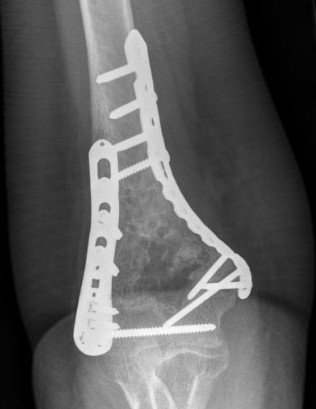

Fixation techniques

Options

Precontoured anatomical plates

Parallel plates v perpendicular plates

Locking v non locking screws

Parallel v perpendicular plates

Parallel plates - medial plate on medial column and lateral plate on lateral column

Perpendicular plates - plates at 90 degrees, with lateral plate posterior